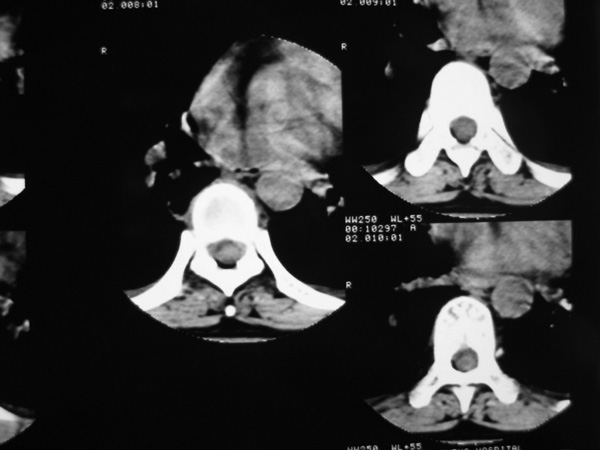

女,45岁,胸背部疼痛2个月。t6、7胸椎病变。

椎旁肿胀的软组织内可见气泡影,对脊柱的化脓性和结核性的鉴别有帮助吗?

胸椎结核与脊柱椎体化脓性脊柱炎,从影像特点很难鉴别,本例具有二者的共性特点,建议结合临床鉴别以下,我考虑:1 化脓性脊柱炎.2 胸椎结核.原因:1 椎旁脓肿内含气泡.2 椎体溶骨性破坏,但未见死骨.

胸椎结核与脊柱椎体化脓性脊柱炎,从影像特点很难鉴别,本例具有二者的共性特点,建议结合临床鉴别以下,我考虑:1 胸椎结核.2 化脓性脊柱炎.原因: 椎体溶骨性破坏,但未见死骨.我认为大家说的气泡是假象。